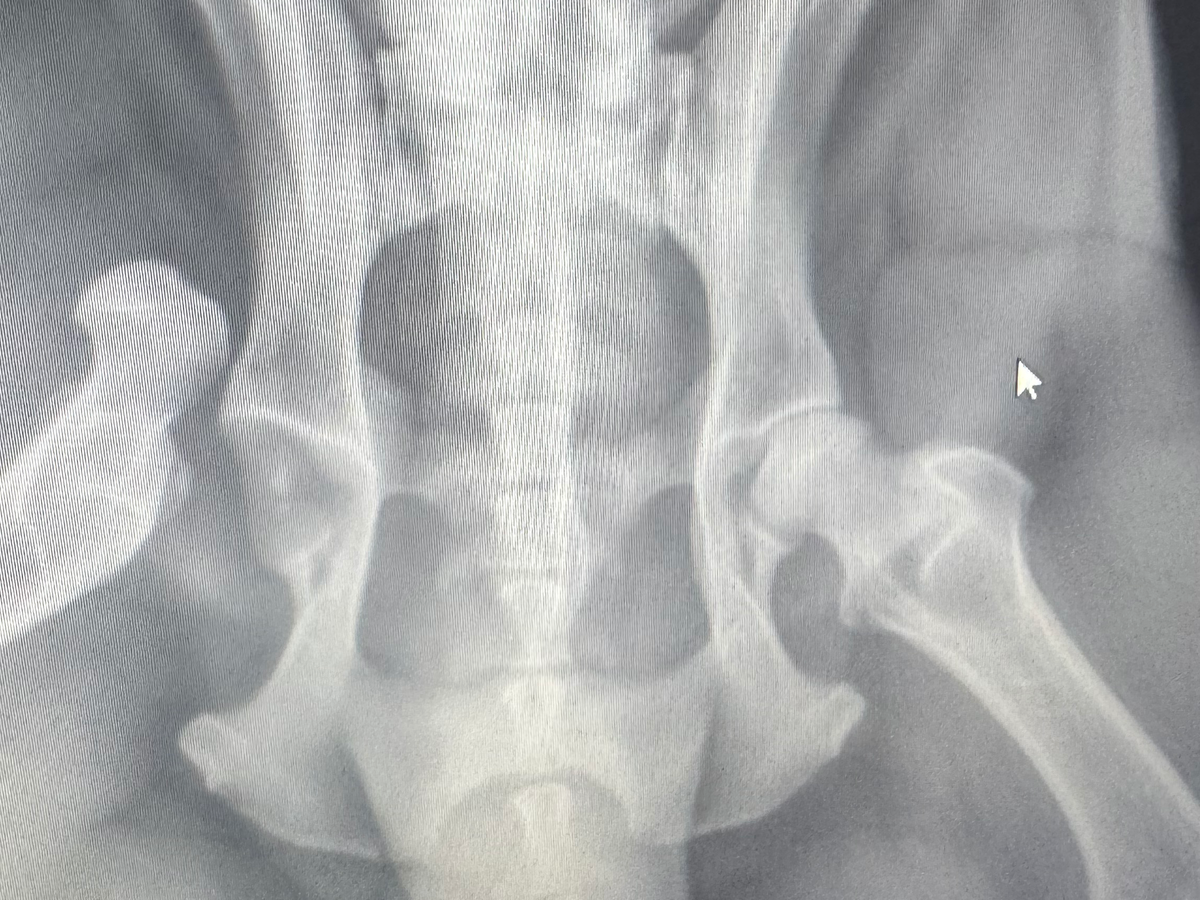

My beautiful dog, Rocky, who is three, got hit by a speeding car that never stopped. I tried my best to stand in the road, and the driver wouldn’t stop. I dove out of the way, but Rocky was hit. He needs emergency surgery.